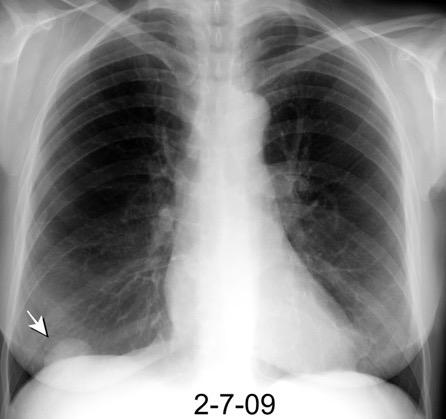

Parálisis frénica transitoria tras cirugía de válvula aórtica

Parálisis frénica transitoria post cirugía cardiaca (10%).

Puede acompañarse de atelectasia del LII.

Benjamin JJ et al. . Left lower lobe atelectasis and consolidation following cardiac surgery: the effect of topical cooling on the phrenic nerve. Radiology 1982